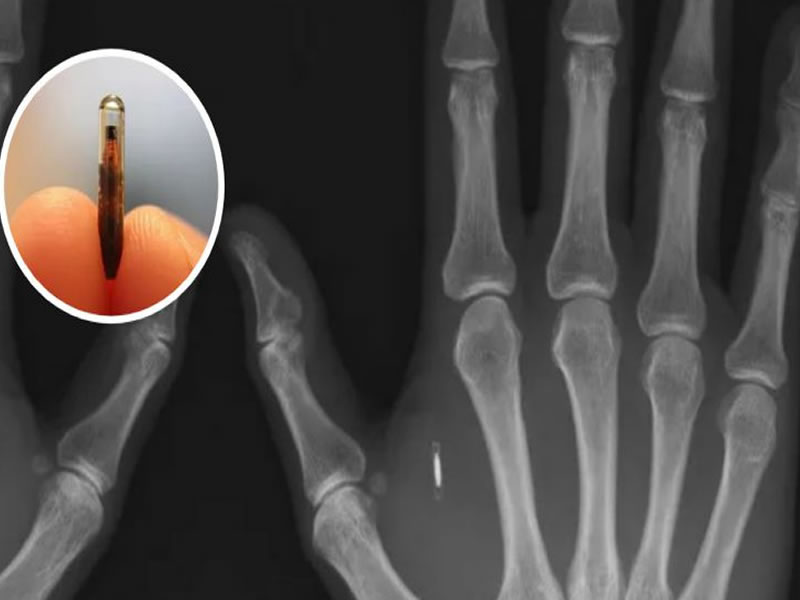

Chip implantado na pele substitui chave e até cartão de crédito e já é realidade no Brasil

A inovação tecnológica consiste na implementação de um chip do tamanho de u...